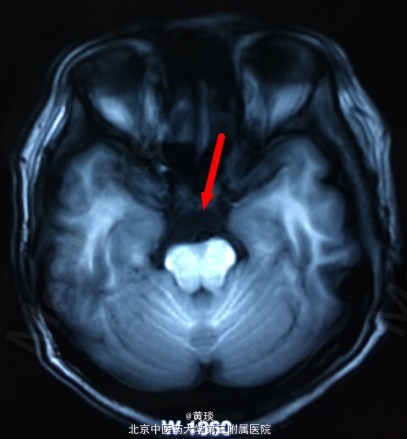

患者女,75岁,自诉压槽疼痛10年,未予重视,曾行封闭治疗无效,来我院,本来诊断为普通三叉神经痛,结果行MRI示:桥小脑角区占位,胆脂瘤,T1相高信号,T2相低信号,抑脂相高信号,压迫右侧三叉神经。

见图

诊断:胆脂瘤,继发三叉神经痛 处理:开颅切除胆脂瘤